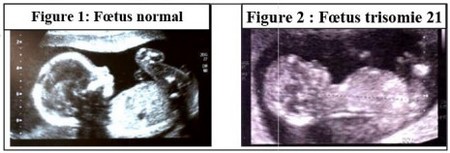

Examen par la technique d’échographie

L’échographie est une technique d'imagerie employant des ultrasons.

L’échographe est constitué d’une sonde, permettant l’émission et la réception d'ultrasons et un système transformant le délai entre l'émission et la réception de l'ultrason en image :